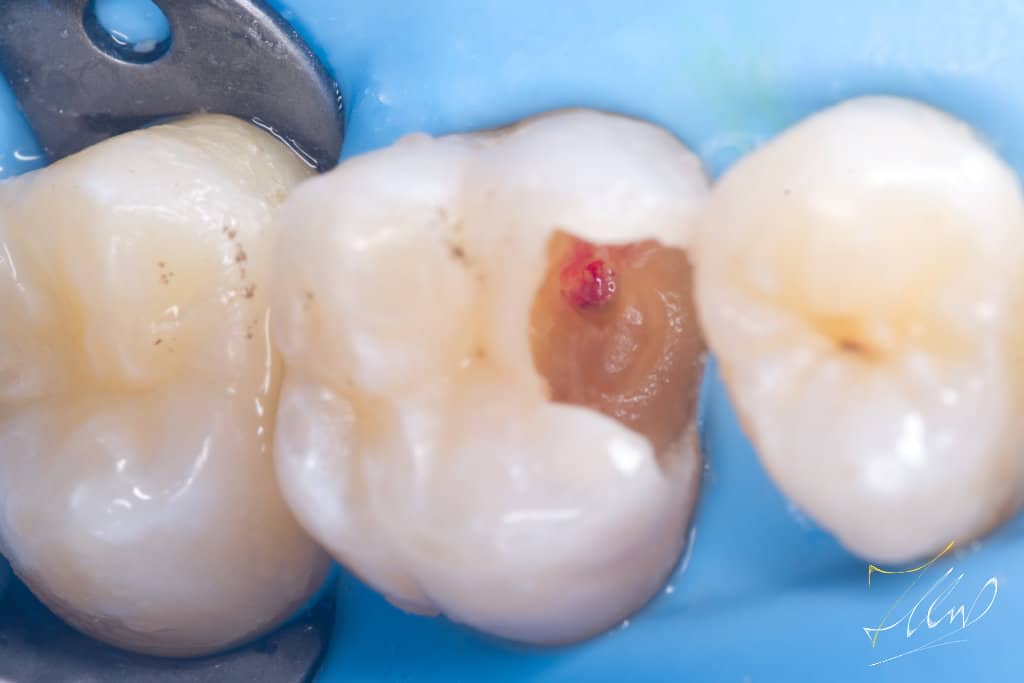

When caries are removed and the pulp is exposed, it can weaken the enamel. In such cases, it is advisable to create a silicone index after covering the exposed pulp with mineral trioxide aggregate (MTA). This should be followed by a precise cavity design and the removal of unsupported buccal cusp .

Final cavity design.